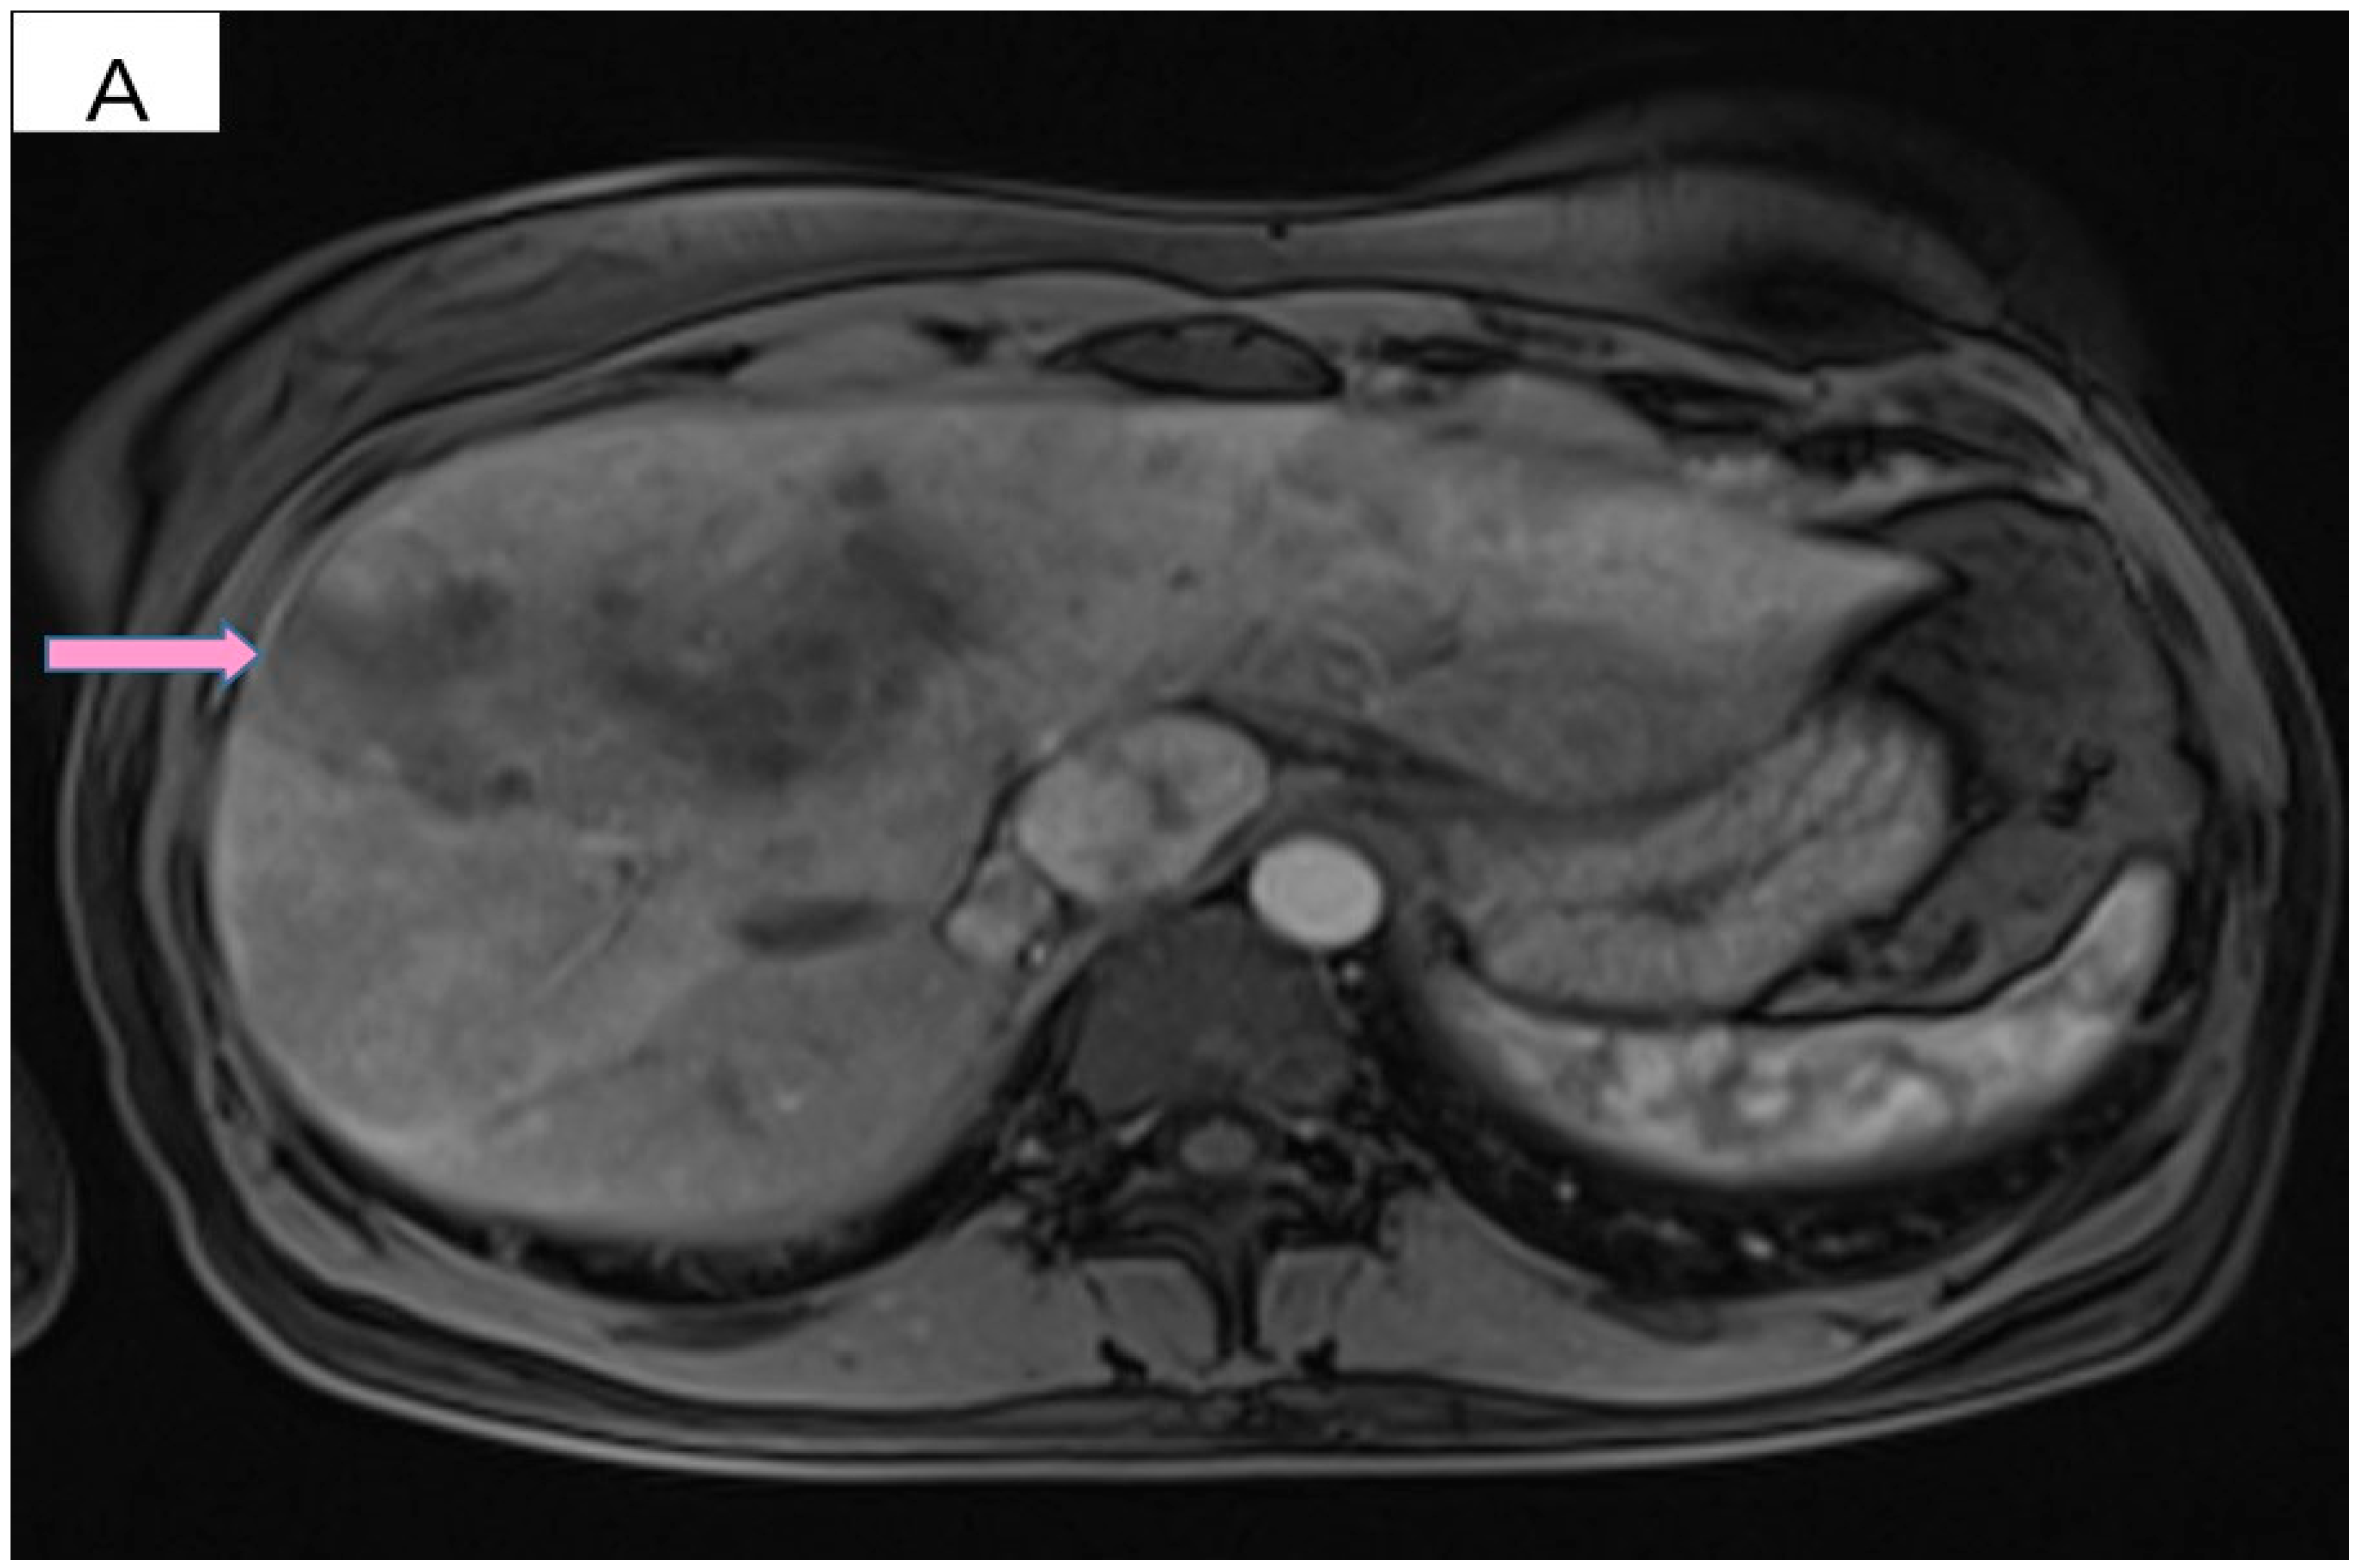

However, 2 years after the initial diagnosis, in February 2021, during the clinical and biological evaluation for an expander replacement, lab reports highlighted abnormal values of the liver enzymes—aspartate aminotransferase (AST) 155 UI/L and alanine aminotransferase (ALT) 114 UI/L. After excluding an infectious or toxic etiology, an abdominal ultrasound revealed the presence of hepatic metastases in the eighth hepatic segment. An abdominal MRI was immediately requested which showed a liver tumor mass of approximately 9.6/6.6 cm with the aspect of liver metastasis (Figure 3A). Subsequently, chest CT revealed carcinomatous lymphangitis (Figure 4A) and millimeter areas of osteolysis in the T1 and L1 vertebral bodies and the sternal body, without brain metastases on cerebral CT. During workup period, the patient’s clinical status worsened by developing symptoms of respiratory failure with dyspnoea at minimal exertion with oxygen saturation (SaO2) of 75% and rapid progressive dry cough. Furthermore, the liver was palpable 6 cm below the costal rim. Hepatic assays were exacerbated by a severe increase in AST 635 UI/L and ALT 309 UI/L (Figure 5), but with normal value of total bilirubin 1.14 mg/dL, alkaline phosphatase 179 U/L and gamma-glutamyl transferase 154 U/L with slightly increased values, albumin 3.01 g/dL, International Normalized Ratio (INR) 1.2. Tumor marker CA 15-3 was also increased (286 U/mL). At that time, the prognosis was extremely reserved.

Figure 3.

(A) Pretreatment MRI scan of the abdomen showing a large hypodense mass in the left lobe of the liver—segments VIII and IV (marked by arrows). (B) MRI scan showing a dramatic decrease in size of the metastasis (marked by arrows) in the left lobe of the liver after treatment with six cycles of Pertuzumab, Trastuzumab and Paclitaxel.